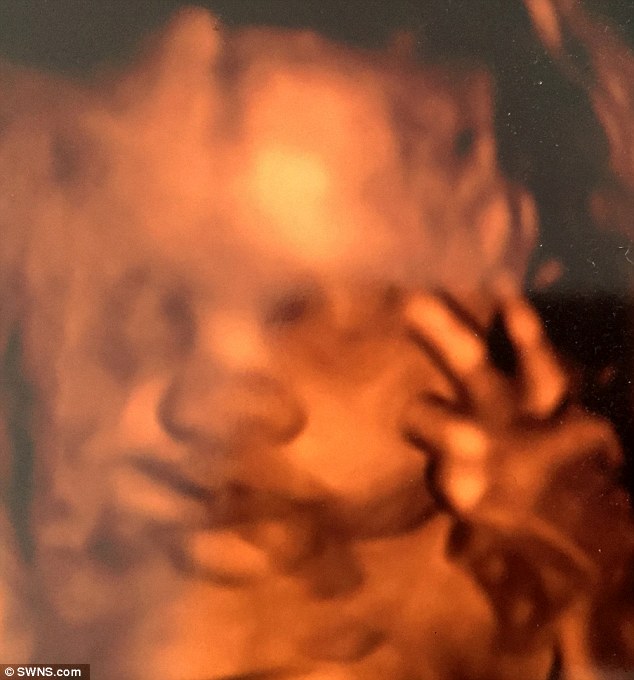

BRISTOL – Una coppia di genitori di Bristol, ha raccontato il loro stupore dopo aver visto il figlio non ancora nato che saluta i genitori con due dita da dentro la pancia.

Aimee Ford è andata a fare un’ecografia al settimo mese di gravidanza insieme al marito Russ Worlock. I due hanno raccontato di essere rimasti completamente scioccati dopo aver visto il loro terzo figlio che saluta mostrando due dita vicino al volto. I due hanno raccontato di aver riso: “La nostra ecografia del settimo mese di gravidanza, resterà per sempre indimenticabile. Io proprio non me l’aspettavo” ha detto la donna già madre di due figli: Evelyn che ha 4 anni e che ha partecipato all’ecografia, ed Edward nato nel mese di novembre.

Il feto che saluta la mamma con due dita6